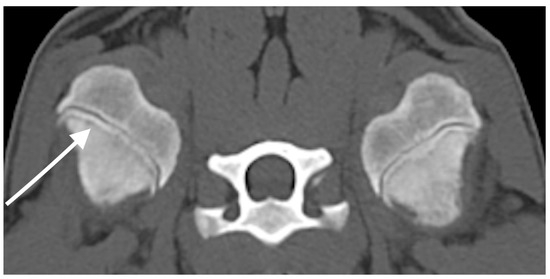

A full-body CT study was performed before and after intravenous administration of iodinated non-ionic contrast medium. CT findings revealed bilateral, symmetrical metaphyseal changes affecting the proximal humerus, distal radius and ulna, proximal and distal femur, proximal and distal tibia and fibula, and distal metacarpal and metatarsal bones. These changes included an irregular, thin hypoattenuating metaphyseal band of lysis parallel to the physis, associated to a zone of metaphyseal increased attenuation consistent with bone sclerosis (Figure 1 and Figure 2A). The bones were affected to different degrees, some of the changes were very subtle, and the distal ulnae were most severely affected. Very mild new bone formation was incompletely encircling several metaphyses, likely representing normal cutback zones or early paracortical cuffs. No abnormalities were observed within the joints or subchondral bone, and no abnormal contrast enhancement was detected. Mild generalised lymphadenomegaly was present, which was considered a normal age-related finding, or mild reactive hyperplasia. Mild bilateral hypoattenuating foci were present, affecting both mandibular condyles with very mild irregularity of the subchondral bone. The overall imaging findings were suggestive of MO.

This study describes the imaging findings of four dogs with presumed diagnosis of MO based on CT images. In all cases, bilateral, irregular, hypoattenuating metaphyseal bands of lysis were observed, running parallel to the physis. These lesions were symmetric, often bordered by areas of metaphyseal sclerosis, and commonly associated with mild periosteal new bone formation. Despite the consistent nature of these imaging features, the severity of the lesions varied both within individual patients and across the different cases. Subtle changes, such as those shown in Figure 1, may represent early manifestations of MO and are unlikely to be detectable on plain radiographs.

Figure 1. Case 1. Transverse CT image of the proximal humeri with bone algorithm reconstruction at initial presentation. Bilateral symmetric thin hypoattenuating metaphyseal band is present parallel to the physis (white arrow).